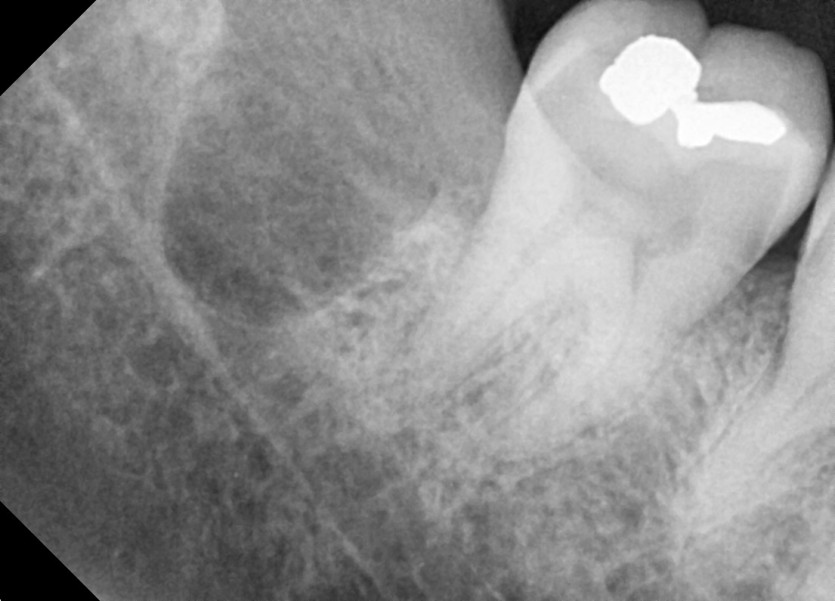

#28,38,48 사랑니 발치

구강 외과 전문의가 당일 발치했습니다.